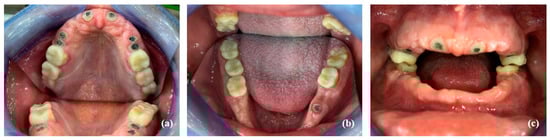

- Pre-prosthetic care: exodontia, endodontic and restorative treatments were performed under general anesthesia. The following procedures were performed: endodontic treatment and bonded amalgam restorations for overdenture abutments of teeth numbers 11, 14, 15, 21, 24, 25 and 45 and exodontia of 46, 44, 43, 41, 33, 34, 35, 23, 22, 13 and 12 (Figure 6). The TRPD were placed on the day of surgery and a postoperative consultation was performed the following day to evaluate and adjust the prostheses (Figure 7).

- Fabrication of definitive removable partial dentures: the definitive prostheses were fabricated using the conventional technique from functional impressions. The patient’s new smile is shown in Figure 10.